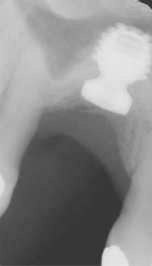

Presentamos el caso de un paciente masculino de 69 años, en el que se realizó la extracción dental seguida de la colocación de un implante Bicon SHORT® de 6,0 x 5,0 mm con pilar de elevación de seno.

El caso se restauró con una corona de pilar integrado (IAC) de 20 mm de longitud y ha sido seguido durante 84 meses.

Este caso destaca no solo por la estabilidad a largo plazo del implante corto, sino también por mostrar de forma radiográfica la aplicación de la Ley de Wolff: el hueso se adapta y se refuerza en respuesta a la carga funcional.